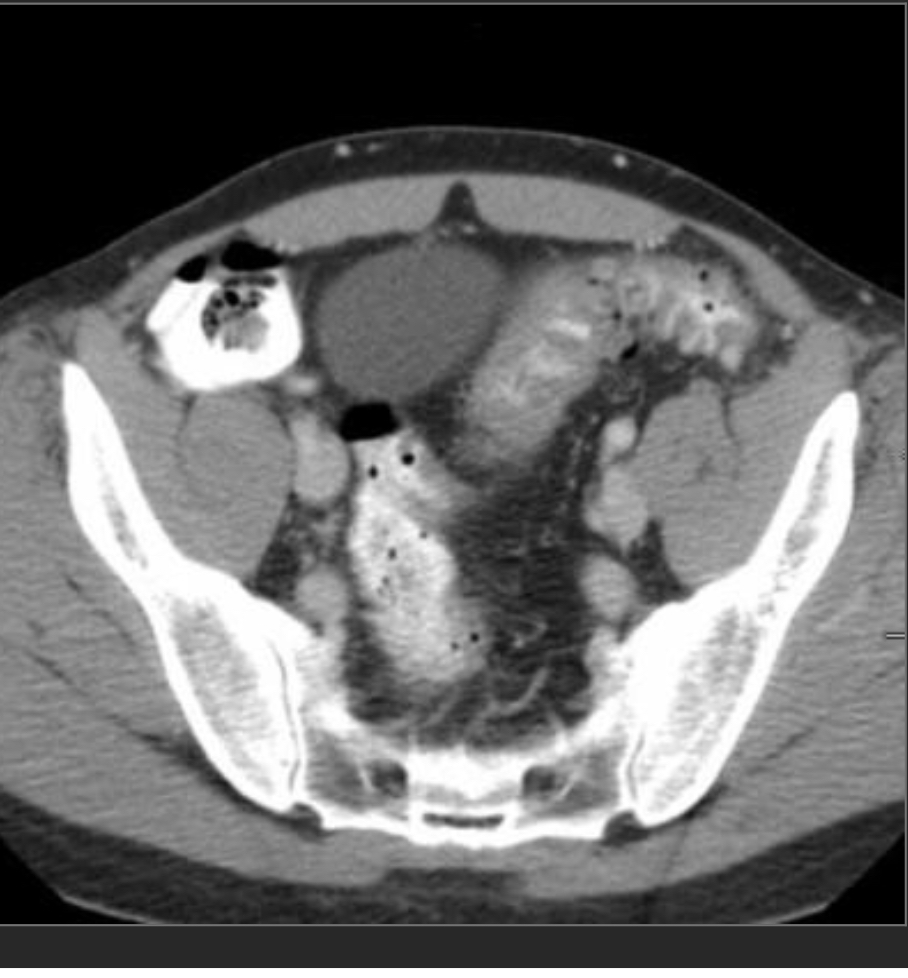

Closed loop obstruction

There is a cluster of fluid-distended loops of small bowel in the pelvis that are notable for relative absence of intraluminal gas, minimal enhancement of their mucosa, infiltrated mesentery, engorged mesenteric vessels and interloop ascites. The distal small bowel is of normal caliber.

—> findings suggestive of ischemia/closed loop include minimal enhancement of the mucosa and engorged mesenteric fat/vessels, and focal ascites.

—> in pt w/appropriate hx could also be a post-op intramesenteric hernia